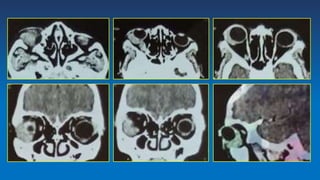

Diagnostic approaches

• An abdominal and orbital mass with

proptosis and hyperglobus (unilaterally or

bilaterally) in an African child is highly

suggestive of diagnosis.

• Orbital CT and MRI demonstrate a maxillary

mass with secondary orbital involvement.